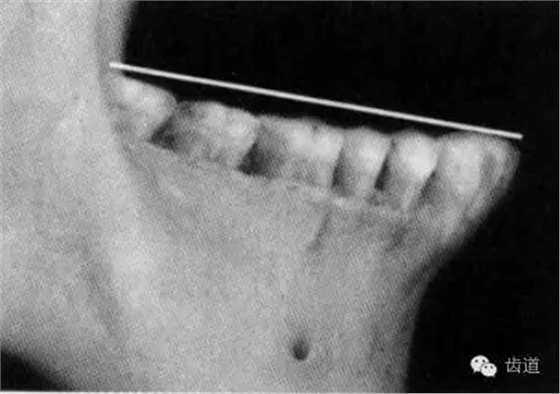

HE平面是一個假想的平面,用來描述上、下頜牙切緣或牙尖排列高低時的一個參考平面。一般指上頜中切牙的近中切角到雙側(cè)第一磨牙的近中頰尖或者近中舌尖,或者遠中頰尖,連接成的平面,該平面基本與鼻翼耳屏面平行。在無牙頜的患者進行禾修復(fù)時,首先需要確定的,就是這前方一個點,后方兩個點所構(gòu)成的平面。以此作為修復(fù)的基準,設(shè)計和修復(fù)喪失的上下牙列。

關(guān)于HE平面,有下面這些描述: 1.前端與瞳孔連線平行,于唇下2毫米。平行表現(xiàn)的是水平無傾斜,應(yīng)該是平行于面部的水平線,有可能是瞳孔連線,也有可能是口角連線。唇下2毫米,是年青人的美學(xué)表現(xiàn),對于老人,齊平上唇也許更加美觀,以“f/v”的發(fā)音狀態(tài),確定HE平面的前點更為符合生理學(xué)規(guī)律。 2.上頜最后端,離開翼上頜切跡5毫米。這是一個平均值,有可能在5~7毫米內(nèi)調(diào)整,使得后端平面與鼻翼耳屏線平行。 3.下頜后端,平齊于雙側(cè)磨牙后墊高二分之一。這也是平均值,具體要在患者口內(nèi)做調(diào)整。 4.下頜后端在患者口內(nèi)調(diào)整,使之平齊于舌的外側(cè)緣。過高不利于舌在咀嚼中的輔助運動,過低有可能咬舌。 5.調(diào)整下頜前端平面,使下頜前端略高于下唇上緣,與唇平線平行。 6.HE平面盡量平分頜間距離,與牙槽嵴呈相對平行的狀態(tài)。這是從力學(xué)平衡的原理,對HE平面的要求,能使義齒在使用中更加穩(wěn)定。